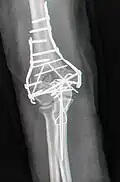

-

Zuggurtung des Olecranon